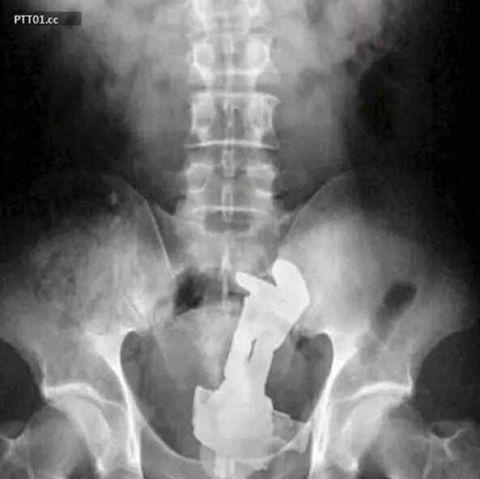

一把钥匙

一把搅拌器